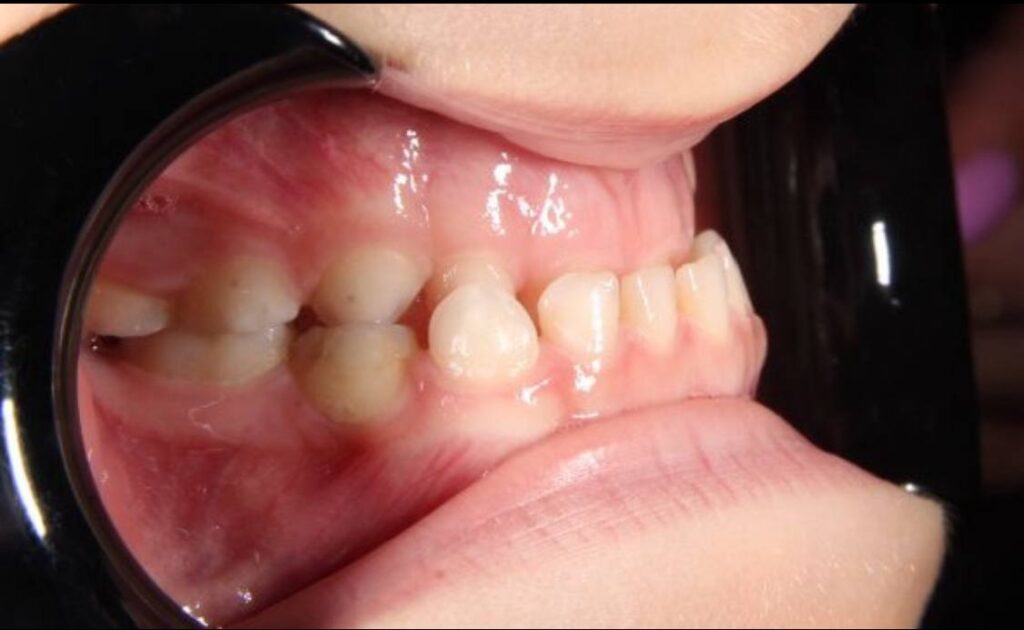

A mother brought her 6-year-old son to the Dynasty Stomatology clinic. She was confused: her son had already been examined at two other clinics, but the proposed options for correcting his jaw condition did not inspire confidence. One medical facility offered an outdated treatment plan involving a cap to restrain jaw growth. The other honestly admitted that they did not know how to proceed and referred her to our orthodontist specialising in jaw skeleton development pathologies.

The mother had a clear request: to solve the problem of massive underdevelopment of the upper jaw against the background of excessive growth of the lower jaw. The child had no significant aesthetic complaints, but even at that stage, it was noticeable that the bite was forming incorrectly. The family’s expectations were to normalise the development of the facial bones, avoid surgery in the future, and preserve the functionality of the bite.

The results of the study confirmed the complexity of the case: without active intervention, the patient would have required double jaw surgery after 18 years of age.

- The shape of the child’s face improved — this was noticed not only by doctors, but also by her parents.

- The growth of the upper jaw normalised, and the pressure on the lower jaw decreased.

- We prevented the formation of severe deformity, which would have required surgical intervention in adulthood.